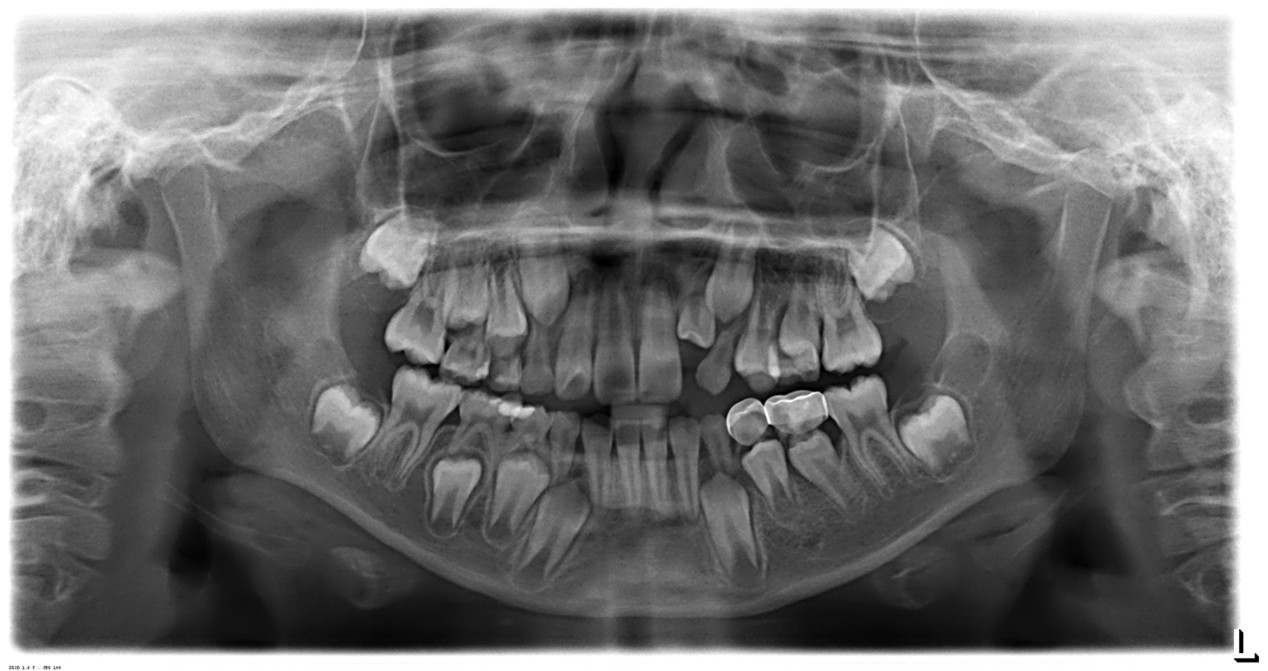

此張x光片為學齡小孩恆牙,乳牙交換期間拍攝,可供醫師參考治療方案

1. 牙齒發育評估:孩子的牙齒在成長過程中會不斷發育,牙醫師透過X光可以評估恆牙的生長情況,檢查乳牙的脫落是否正常。及早了解牙齒的發育狀態,能夠及時發現異常,以便及早介入。

4. 牙齒排列和咬合:如果孩子的牙齒排列不整齊或咬合不正,這可能會影響口腔功能及美觀。X光檢查可以幫助牙醫師評估牙齒的排列情況,必要時提出矯正建議,進而增進孩子的口腔健康和自信心。

6. 智齒發育:對於年紀稍大的孩子,X光可以幫助檢查智齒的發育情況及是否需要拔除。